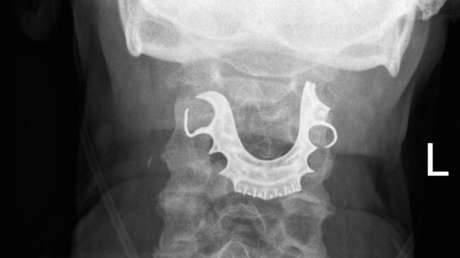

Dos días después regresó al centro de salud porque sus síntomas se habían agudizado: no había podido siquiera ingerir los medicamentos, tenía dificultad para respirar, principalmente al estar acostado, y el sangrado continuaba. Entonces los especialistas le revisaron la garganta y detectaron un objeto extraño sobre sus cuerdas vocales. Luego de una radiografía de cuello se pudo comprobar que se trataba de una pieza compuesta de tres dientes y un puente metálico.